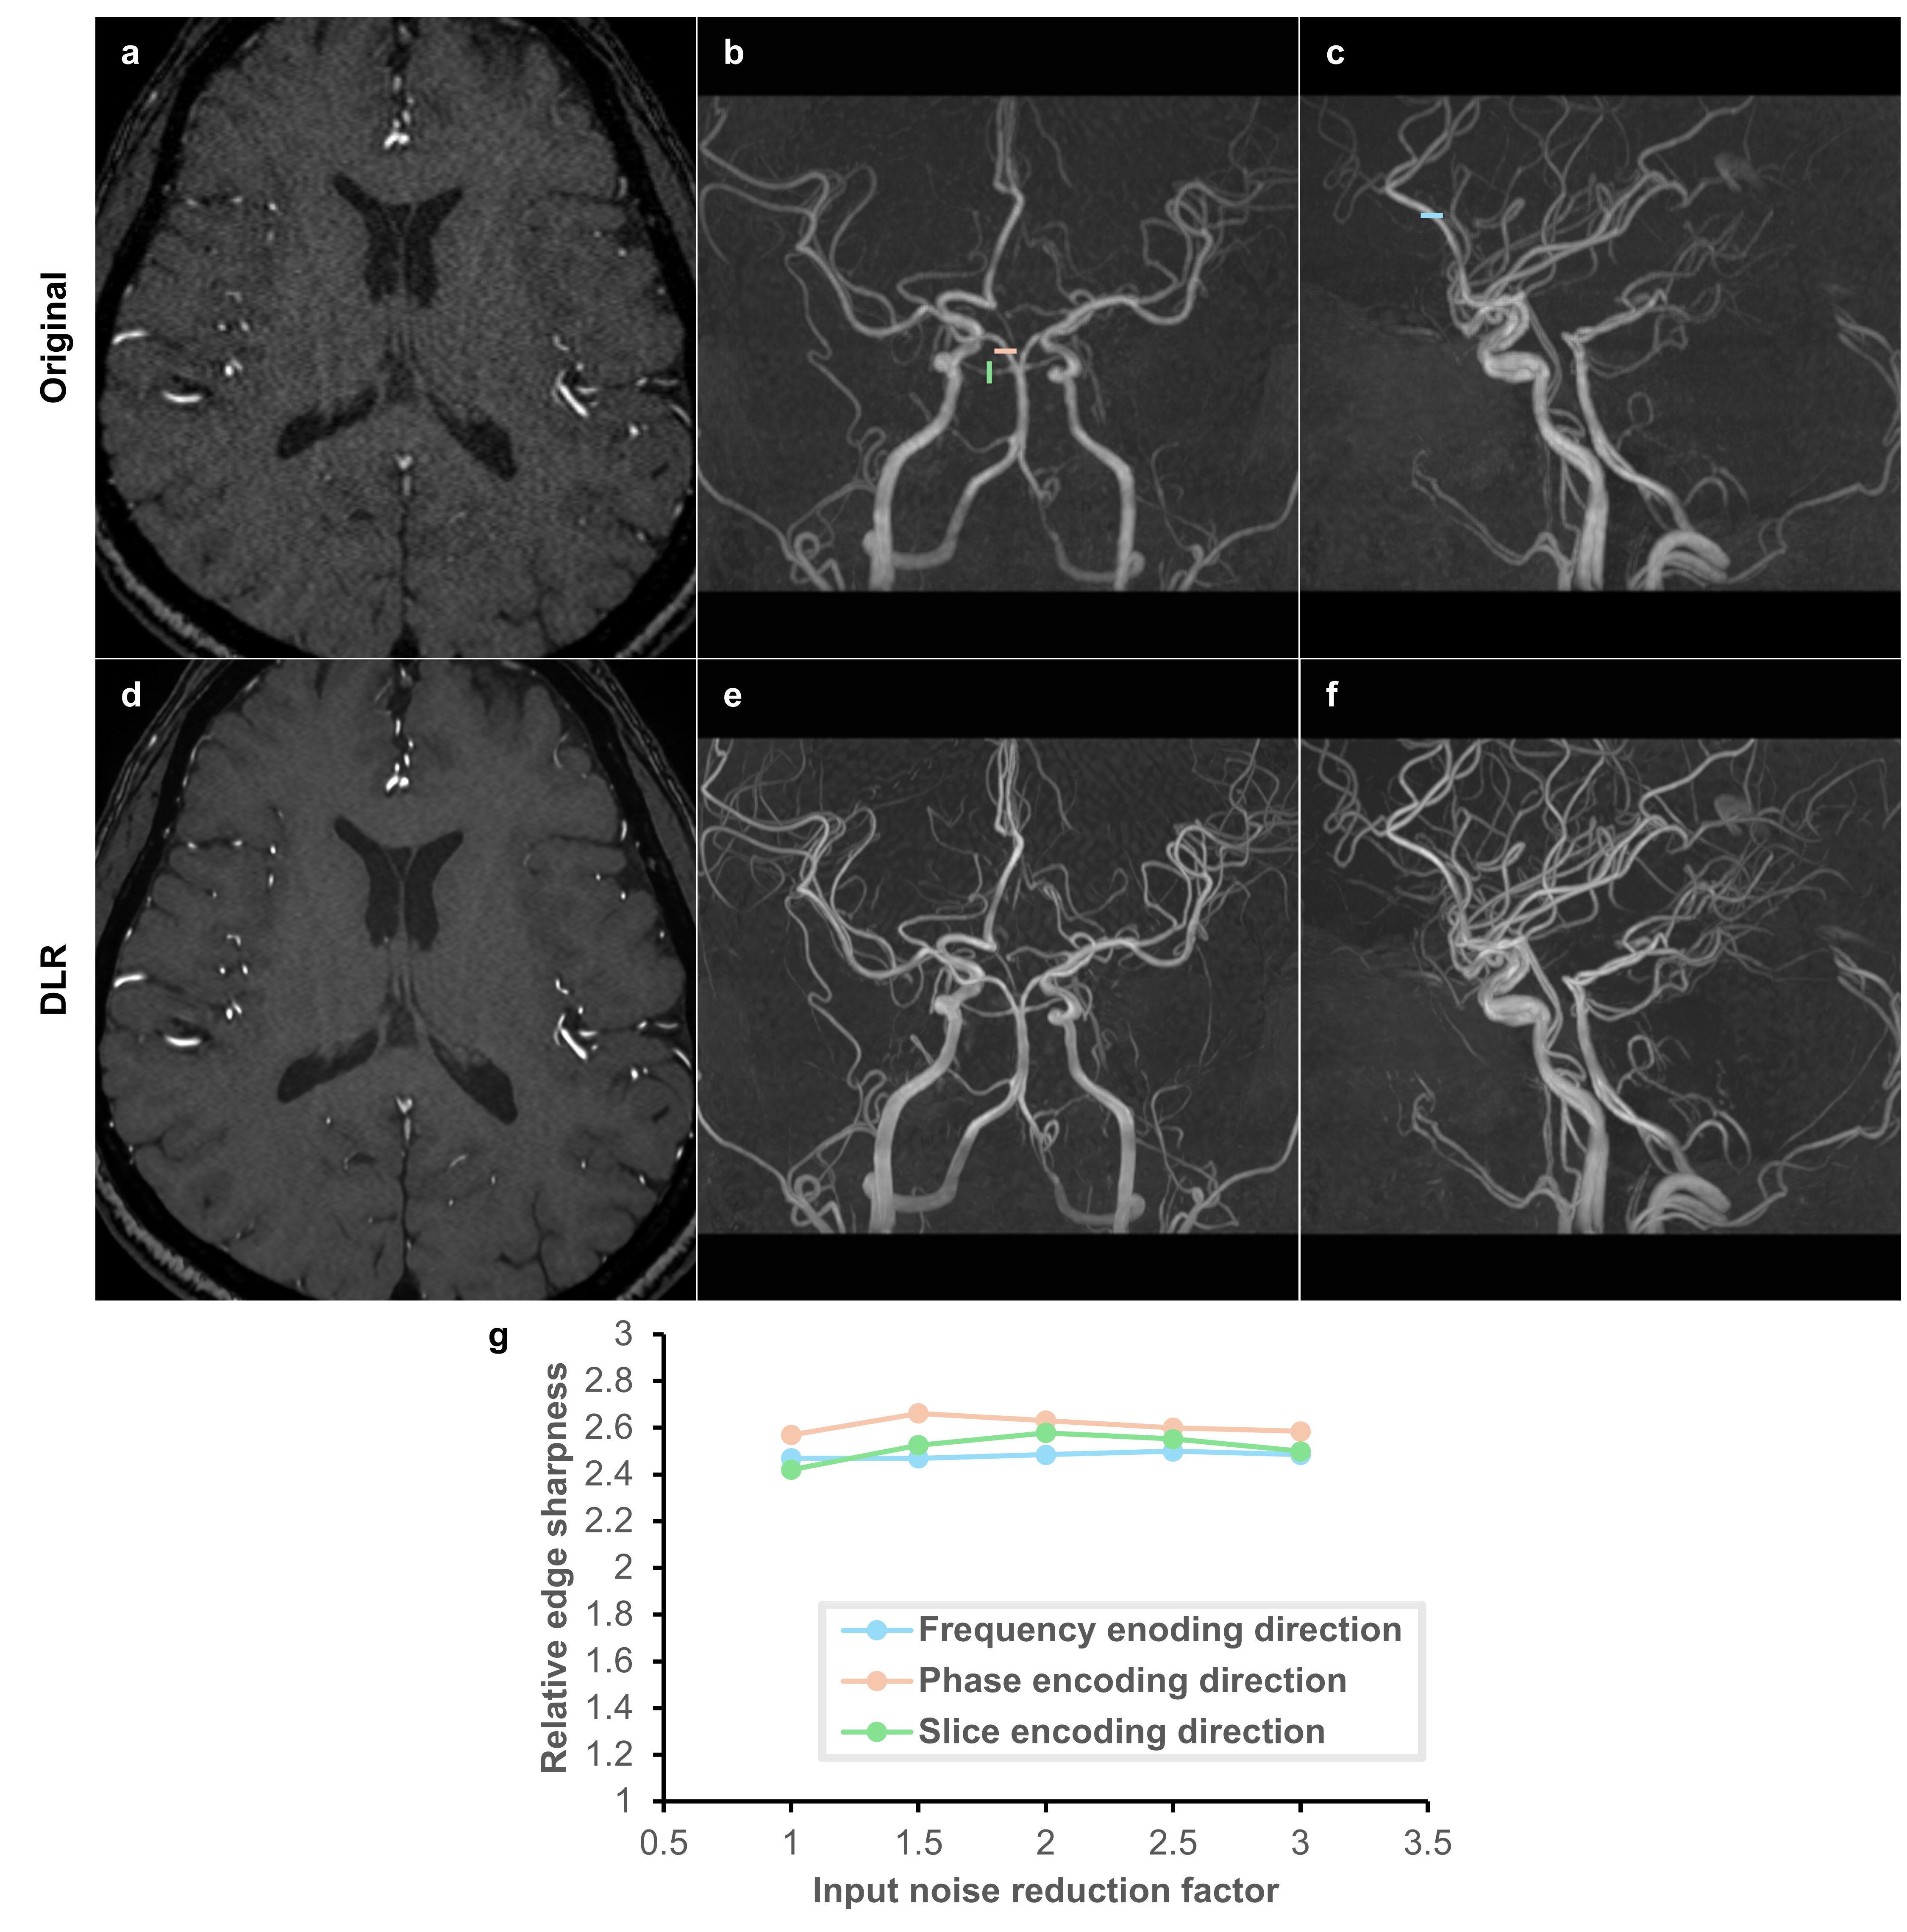

3.3 Super-resolution in all encoding directions

The proposed multi-dimensional image enhancement includes super-resolution in all encoding directions. To verify the effectiveness of super-resolution in each direction, we conducted a quantitative analysis comparing the edge sharpness between original and DLR images. For this purpose, a brain MR angiography (MRA) image was acquired using a 3D time of flight (TOF) pulse sequence on a 1.5 T MR scanner (MAGNETOM Altea, Siemens Healthineers) with a 20-channel head/neck coil. Maximum intensity projection (MIP) images were used to measure edge sharpness due to their abundance of linear structures. The A2 segment of the anterior cerebral artery was selected to evaluate the super-resolution effect in the frequency encoding direction in a sagittal MIP image. Meanwhile, the P1 segment of the posterior cerebral artery and the S1 segment of the superior cerebellar artery were chosen to assess the super-resolution effect in the phase and slice encoding directions, respectively, in a coronal MIP image. The method for computing relative edge sharpness was directly adopted from Lebel’s approach [6]. Line profiles parallel to each encoding direction were plotted across the selected arteries. The relative edge sharpness was then calculated as the ratio of the maximum gradient in these line profiles in the DLR images to that in the original images. Additionally, to investigate the influence of different noise reduction factors on the effectiveness of super-resolution, the source image was DL-reconstructed with variable noise reduction factors of 1.0, 1.5, 2.0, 2.5, and 3.0. DLR MIP images were generated from the DLR source image, rather than by applying DLR directly to the original MIP images.

Figure 5 displays both the original images and the DLR images with a noise reduction factor of 2.5, along with a graph detailing the relative edge sharpness achieved in each encoding direction at various noise reduction factors. A relative edge sharpness of approximately 2.5 was achieved in all three encoding directions, independent of the applied noise reduction factor.

Refer to caption

Figure 5: Relative edge sharpness between original and DLR images in three encoding directions at various noise reduction factors. (a) Original MR angiography source image. (b,c) MIP images derived from (a), with line profiles marked in blue, red, and green for the frequency, phase, and slice directions respectively, used for measuring edge sharpness. (d) DLR image of (a). (e,f) MIP images derived from (d). Comparisons between (a) and (d), (b) and (e), and (c) and (f) reveal marked noise reduction and resolution enhancement in the DLR images. (g) Depicts the relative edge sharpness, measured as the ratio of the maximum gradient in the line profile in the DLR image to that in the original image. A relative edge sharpness of approximately 2.5 was achieved in all three encoding directions, regardless of the applied noise reduction factor. MIP, maximum intensity projection; DLR, deep learning reconstruction.